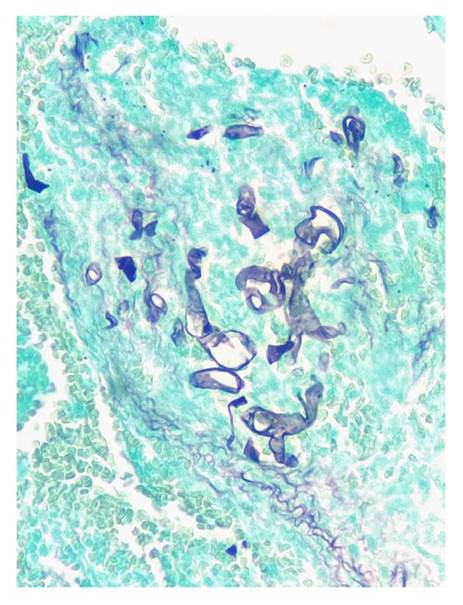

En todos los casos, se identificaron hifas anchas que variaban entre 5 y 20 pm, de contornos irregulares y pleomorfas. Su patrón de ramificación era al azar y, aunque predominaban en ángulo recto, algunas de ellas estaban colapsadas, organizadas en cordones o con doblamiento (figuras 2-5) 1.

Figura 3 Se reconocen hifas hialinas, gruesas, irregulares, seccionadas de forma transversal y sagital. Gomori-Grocott, 40X.

Figura 5 Se identifican hifas hialinas, irregulares, de diferentes formas y paredes gruesas, distribuidas de manera difusa sobre un estroma denso. Gomori-Grocott, 40X.